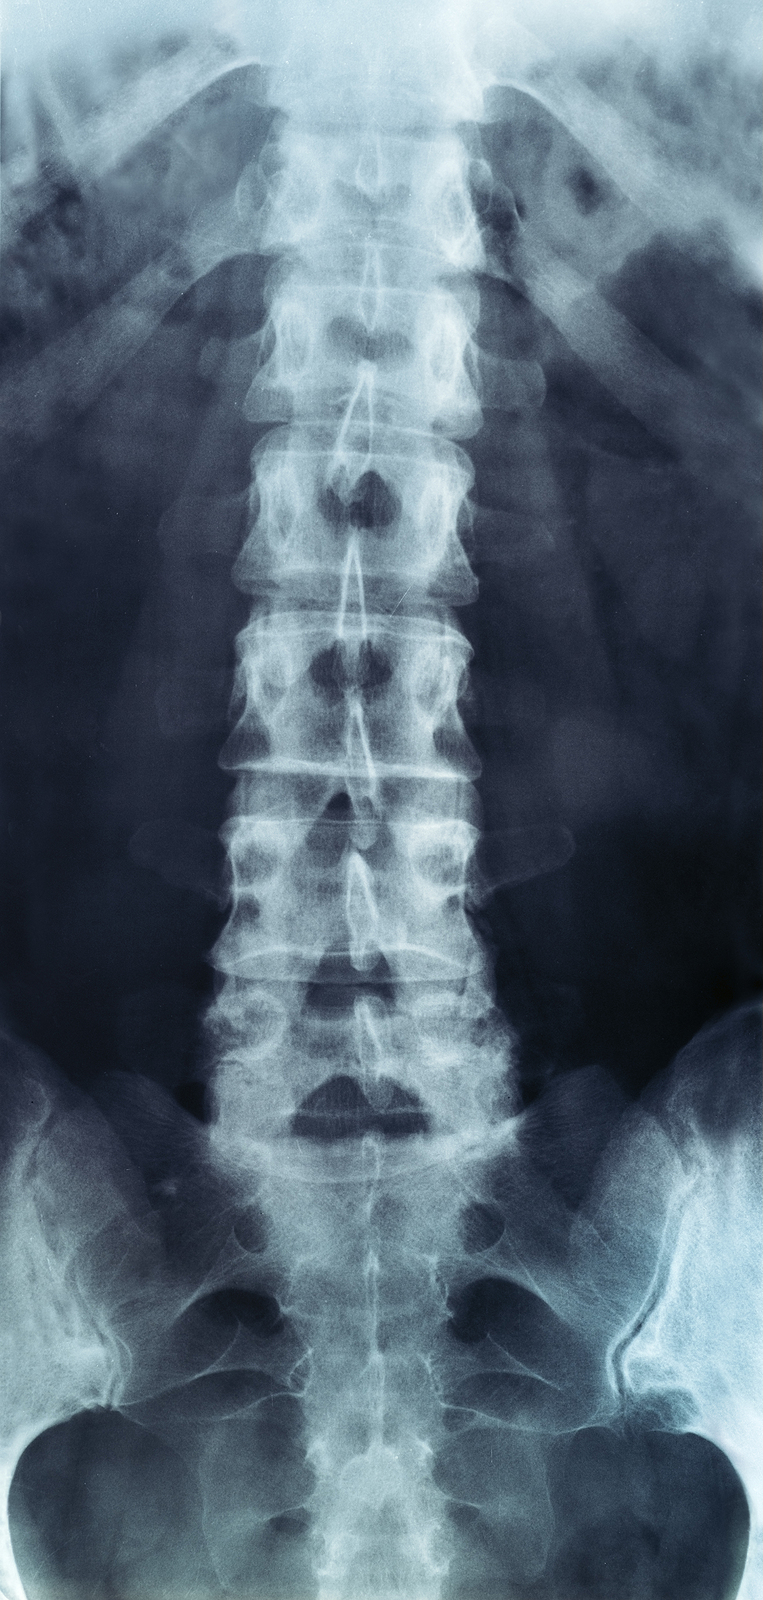

The human spine is made up of 24 spinal bones, called vertebrae, as well as the sacrum and the coccyx. The sacrum is a triangular bone near the bottom of the spine and the coccyx is more commonly known as the tailbone.

Vertebrae are stacked on top of one another to create the spinal column. The spinal column gives the body its form and helps sustain an upright position.

The lumbar spine—where pain is often experienced—is made up of five vertebrae positioned near the bottom of the spinal column. Doctors often refer to these vertebrae as levels L1, L2, L3, L4 and L5. The ‘L’ refers to ‘lumbar’. The lowest vertebra, L5, is connected to the top of the sacrum—a triangular bone at the base of the spine that is located between the two pelvic bones. Some people are born with an extra or sixth lumbar vertebra called L6. Having an extra vertebra doesn't usually cause physical problems.

X-rays

X-rays are usually the first test ordered before any of the more specialized tests are completed. X-rays use electromagnetic radiation to show problems with bones and can also reveal problems such as fractures, infections, or bone tumors. X-rays of the spine can give your doctor information about bone alignment and can demonstrate how much degeneration has occurred in the spine. Both alignment and degeneration can affect the amount of space in the neural foramina and between the discs, which subsequently impacts the nerves in the area. This is important information your health care professional can use to establish a treatment plan.